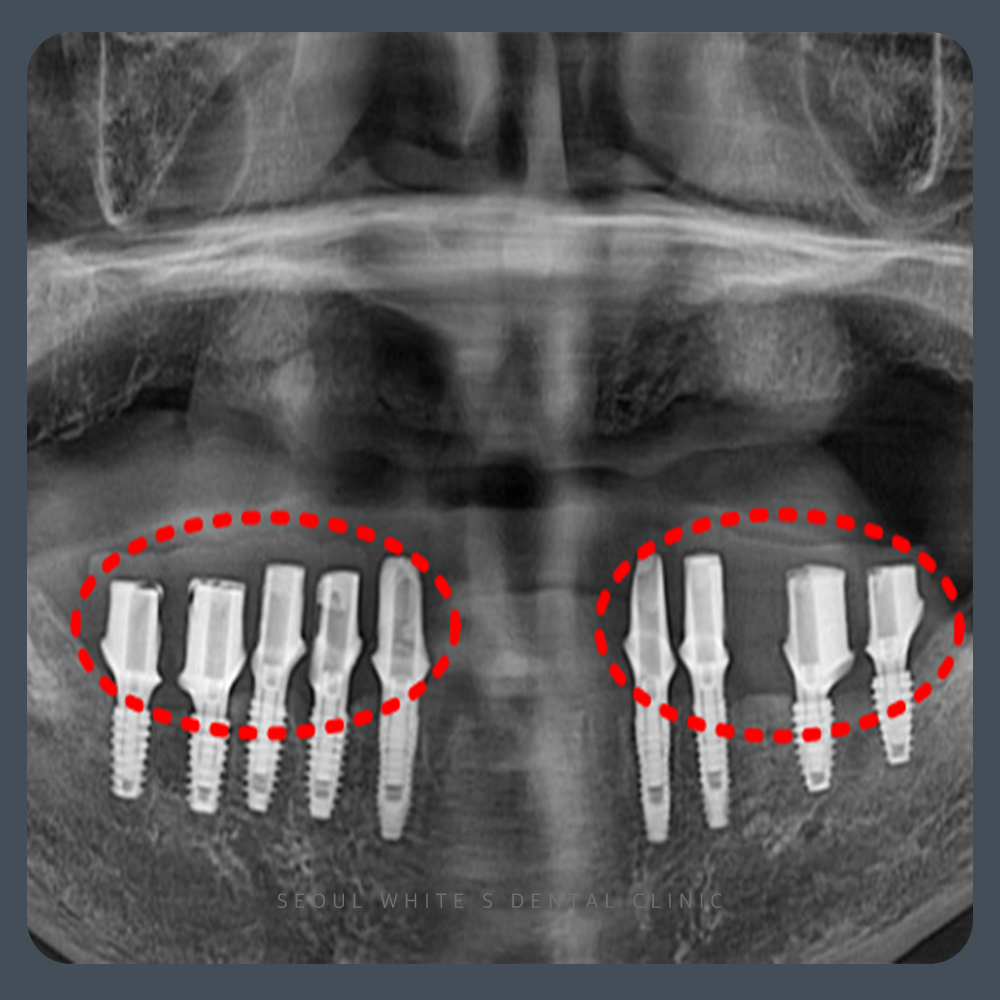

정밀 진단 후, 잇몸뼈 상태를 확인한 결과 식립이 가능한 조건이었기에 디지털 가이드 수술을 계획했습니다.

전악 임플란트는 식립 위치에 따라 결과가 크게 달라질 수 있기 때문에 구강스캐너와 3D CT를 활용한 모의 수술, 그리고 디지털 가이드를 통한 수술 계획이 매우 중요합니다. 이 장치는 환자의 구강 구조를 정확히 반영하여 잇몸을 필요한 만큼 절재하고, 정밀한 각도로 인공치근을 심을 수 있도록 도와줍니다. 그 결과 출혈과 붓기, 통증을 줄일 수 있으며 회복 속도도 빨라집니다.

임플란트 식립 후에는 힐링 어버트먼트를 장착하여 잇몸을 안정적으로 유도합니다. 이 장치는 보철물이 올라가기 전까지, 잇몸 조직을 보호하고 세균 유입을 차단하는 역할을 합니다. 이후 지대주를 결합하고, 환자 맞춤형 보철물을 제작해 최종적으로 심미성과 기능까지 회복하게 됩니다.